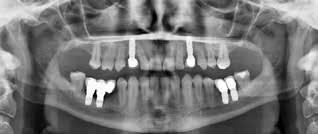

Omhyggelig planlægning før implantatbehandling er afgørende for at kunne træffe det rigtige valg i forhold til behandlingsmetode samt sikre et forudsigeligt behandlingsresultat med en god langtidsprognose og mindst mulig risiko for komplikationer. Dimensionerne, pladsforholdene i mandiblen og afstanden fra toppen af processus alveolaris til den øvre begrænsning af canalis mandibulae er de væsentlige parametre, som har betydning for valg af behandling. I dette temanummer vil tre behandlingsteknikker, som kan anvendes i den atrofiske posteriore mandibel, blive nærmere gennemgået involverende transposition eller lateralisering af NAI (ved en højde af processus alveolaris på ca. 0-4 mm), sandwich-osteotomi (højde på ca. 4-8 mm) og indsættelse af korte implantater (højde på > ca. 8 mm) (Fig. 7). De undersøgelsesmetoder, man vælger i forbindelse med behandlingsplanlægningen, skal gerne være til gavn for patienten og med færrest mulige ulemper. Man skal derfor arbejde

Behandlingsretningslinjer

Fig. 7. Anbefalede behandlingsretningslinjer for implantatindsættelse i den atrofiske posteriore mandibel. Fig. 7. Recommended treatment guidelines for implant placement in the atrophic posterior mandible.